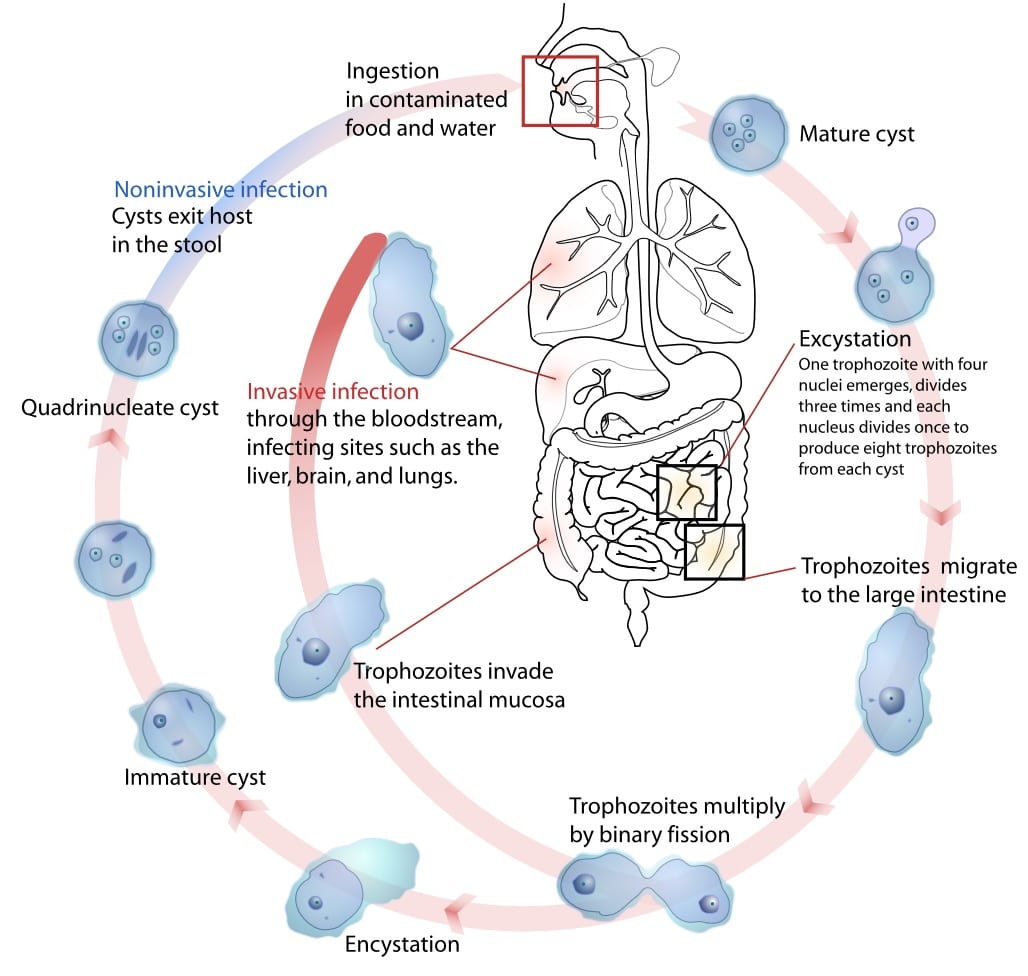

- Norovirus – single-stranded RNA virus (Fig. 1), the most common form of viral gastroenteritis in adults, presents with abdominal cramps, watery diarrhoea, and vomiting, usually lasting 1-3 days

Figure 1 – Rotavirus particles, as seen on electron microscopy

- Entamoeba histolytica – anaerobic amoebozoan that becomes acquired from the ingestion of food or water contaminated with faeces (Fig. 3), presents with bloody diarrhoea, abdominal pain, and fever (can also result in liver abscess); stool culture for ova, cysts and parasites is required for diagnosis, recommended treatment is metronidazole or tinidazole